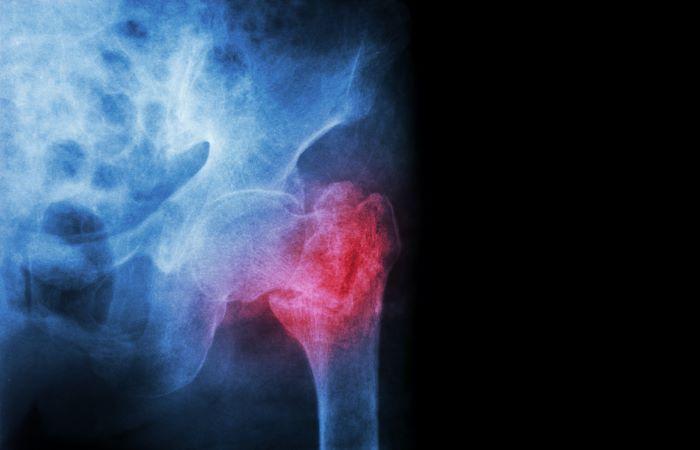

Réduction de la taille, douleurs intenses dans le dos…maladie dite "silencieuse", l’ostéoporose n’en est pas moins un vrai problème pour beaucoup de personnes passé l’âge de 65 ans. Affliction osseuse liée au vieillissement, elle se caractérise par une diminution de la densité de l’os et des modifications de sa microarchitecture. L’os est plus fragile et le risque de fracture augmente. Parmi les facteurs intervenant dans la régulation de la masse osseuse, la vitamine D mais surtout les hormones sexuelles. La maladie est notamment connectée aux changements hormonaux liés à la ménopause et bien qu’elle puisse également toucher les hommes, est surtout répandue chez les femmes ménopausées. Pour donner une idée en termes de chiffres, en Europe et aux Etats-Unis, 30% des femmes ménopausées présenteraient de l’ostéoporose.

Chez certains, la perte de masse osseuse n’aura pas de conséquences graves, mais chez d’autres, l’accélération anormale de la résorption osseuse non compensée par une formation osseuse suffisante entraînera une perte excessive de la masse osseuse et de sa résistance. On parle alors d’ostéoporose. Quand la maladie débute, le médecin traite d’abord une éventuelle carence en vitamine D et ou en calcium, notamment en encourageant son patient à changer son alimentation. Il l’incite également à faire plus d’activité physique, à réduire sa consommation d’alcool et de sel et à arrêter le tabac s’il est fumeur. Mais si la maladie se confirme et empire, il pourra prescrire différents médicaments. Parmi eux, les biphosphonates. Certains ayant associé ces derniers à une chute des dents, Pourquoi Docteur fait aujourd’hui le point.